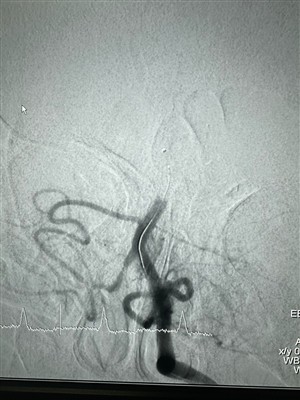

حالات استخدام نظام LAVA Liquid Embolicشارك في جراحة تدخلية حديثة تم إجراؤها باستخدام نظام LAVA Liquid Embolic من NeuroSafe.

أكثر -

حالة باستخدام نظام الصمة السائلة LAVA في إسبانيا64-مريض يبلغ من العمر عامًا مصابًا بتمزق AAA تحت الكلوية (أقصى قطر 79 ملم) وتم علاجه باستخدام EVAR. في مراقبة تصوير الأوعية المقطعية بعد عام واحد، يتم ملء التباين ونمو كيس تمدد الأوعية الدموية (أقص...